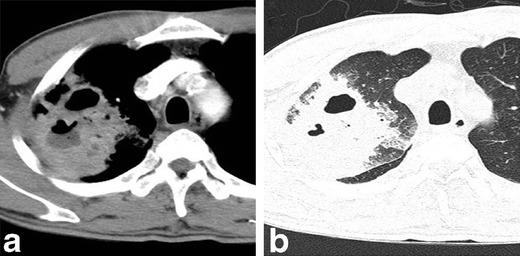

Thoracic actinomycosis can be radiologically divided into the parenchymal type, the airway type including bronchiectasis, the endobronchial form, and the mediastinum or chest wall involvement type.

• Important risk factors for thoracic actinomycosis are underlying respiratory disorders such as emphysema and chronic bronchitis. • Different CT patterns can be distinguished in thoracic actinomycosis: parenchymal, bronchiectatic, endobronchial and extrapulmonary. • Typical CT findings in the parenchymal pattern are a central low density within the parenchymal consolidation and adjacent pleural thickening.

胸放线菌病可在放射学上分为实质型、气道型(包括支气管扩张)、支气管内型和纵隔或胸壁受累型。

• 胸放线菌病可区分不同的 CT 模式:实质型、支气管扩张型、支气管内型和肺外型。

• 实质型的典型 CT 表现为实质浸润内的中央低密度影和相邻胸膜增厚。